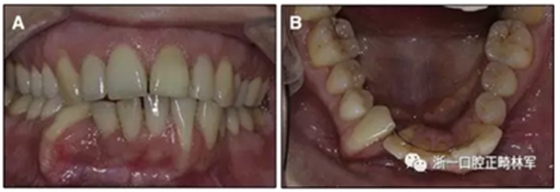

此外,有几篇关于长期使用固定保持器后出现并发症的报道被发表。在严重情况下,“非设计性主动保持器”几乎可以完全将牙根部移出牙槽骨(图1)。